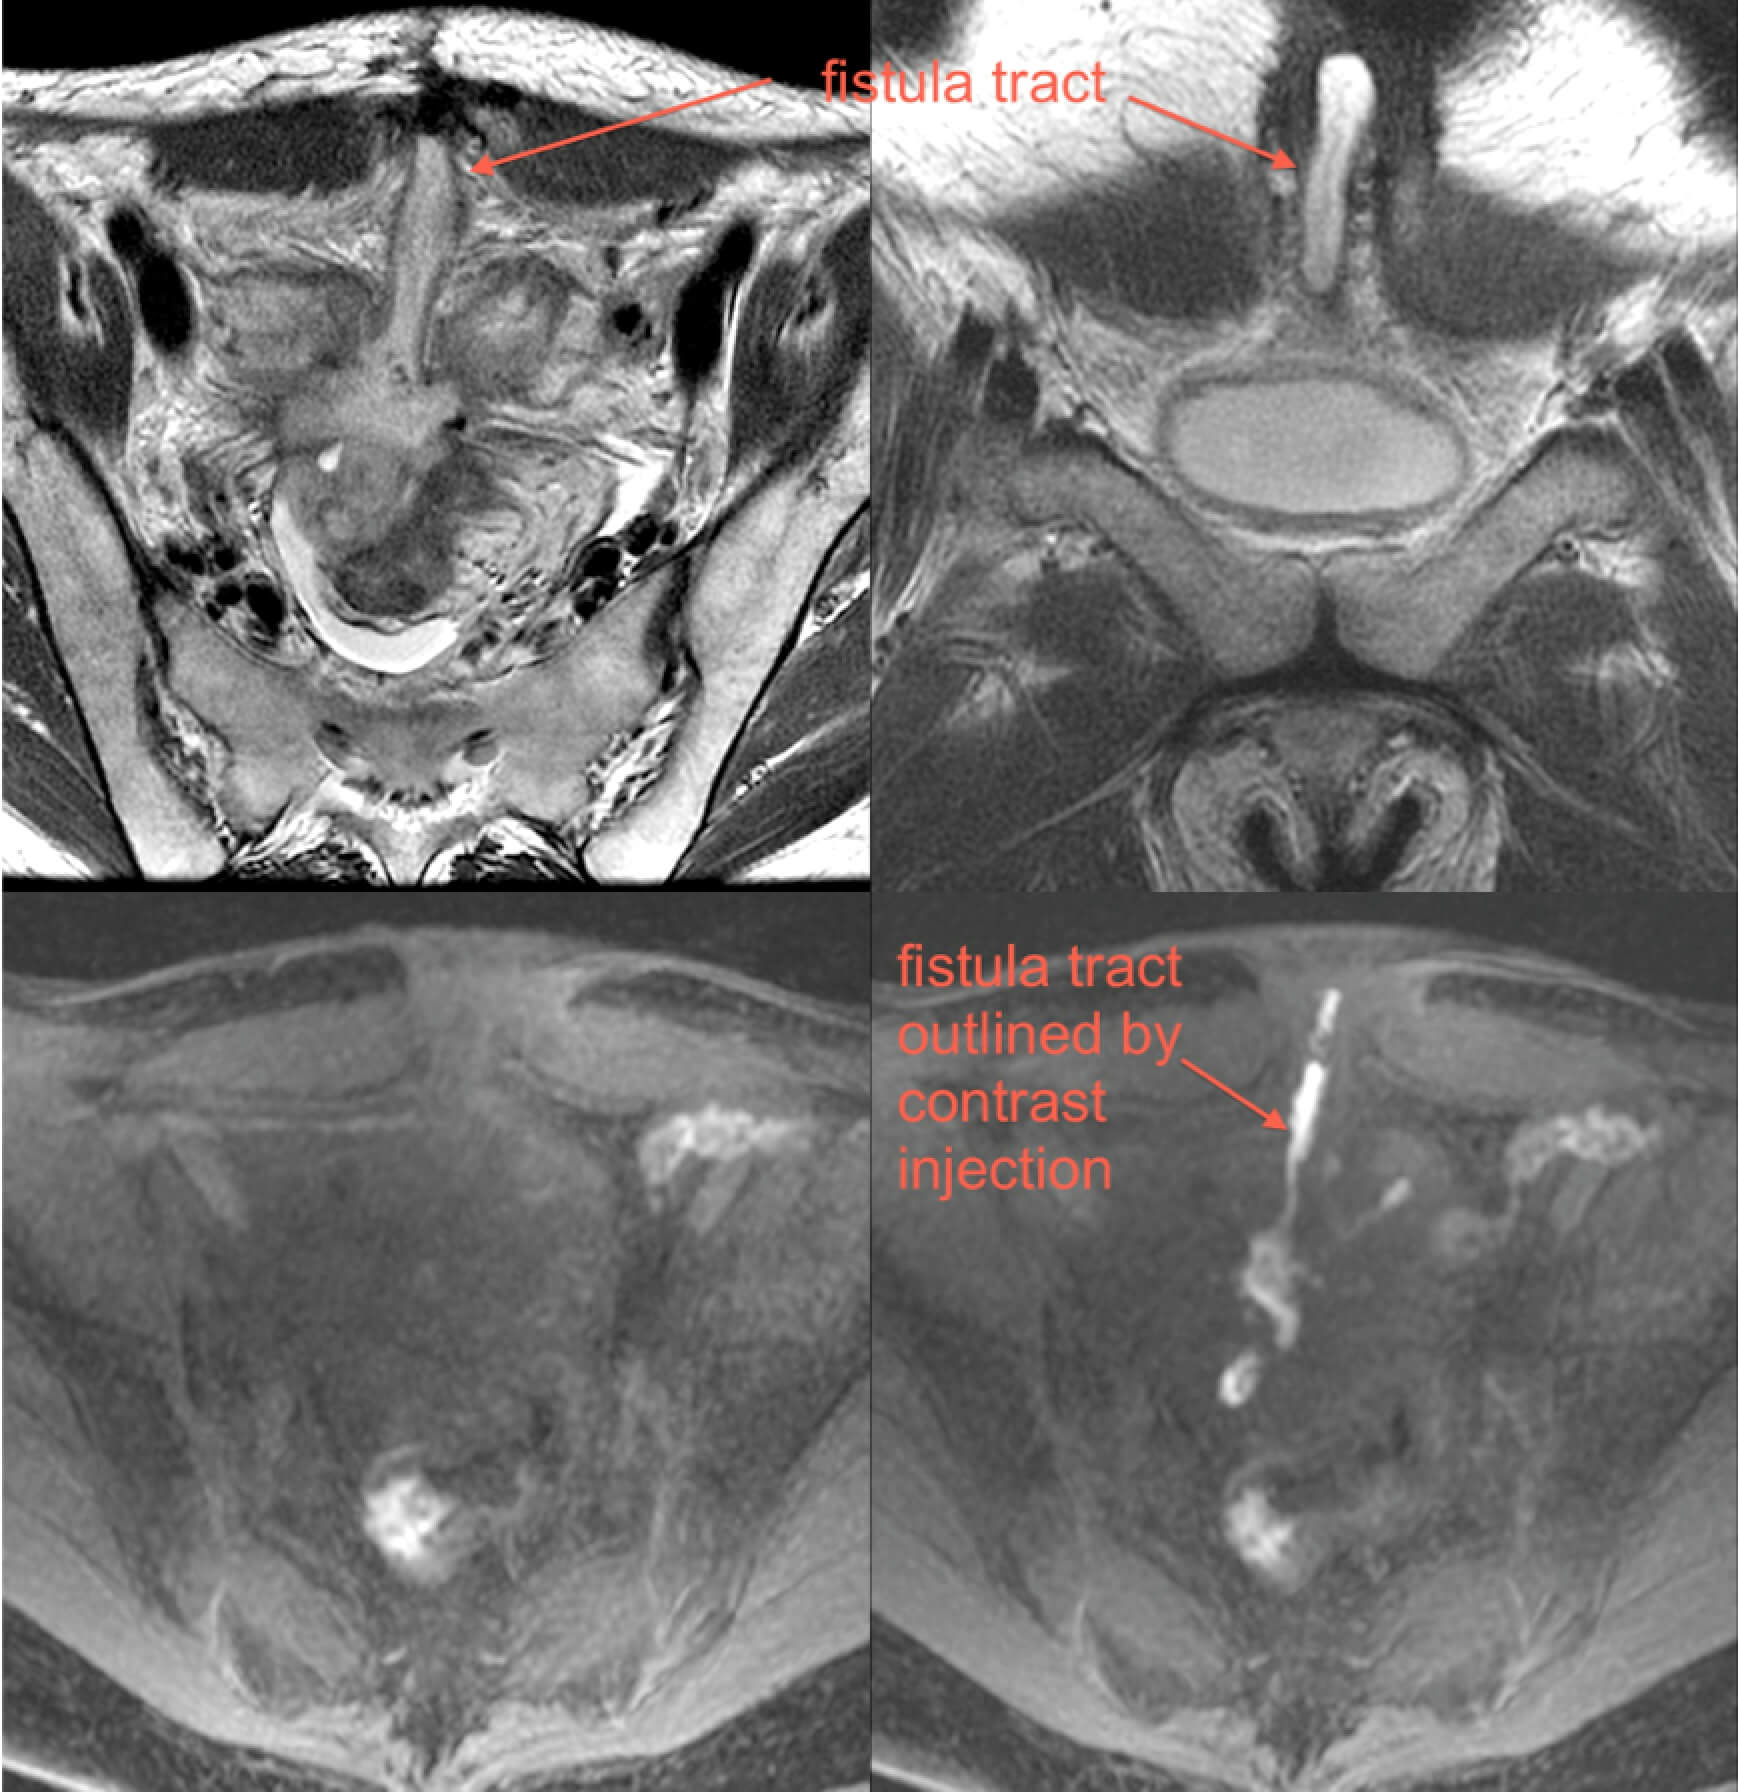

MR enterography is valuable for determining extent of inflamed bowel, discriminating between active inflammation and chronic fibrosing disease, detecting fistulae, and detecting strictures. Additionally, MRI can provide excellent delineation of the course of perianal fistulas, including relationships to sphincters and levators.